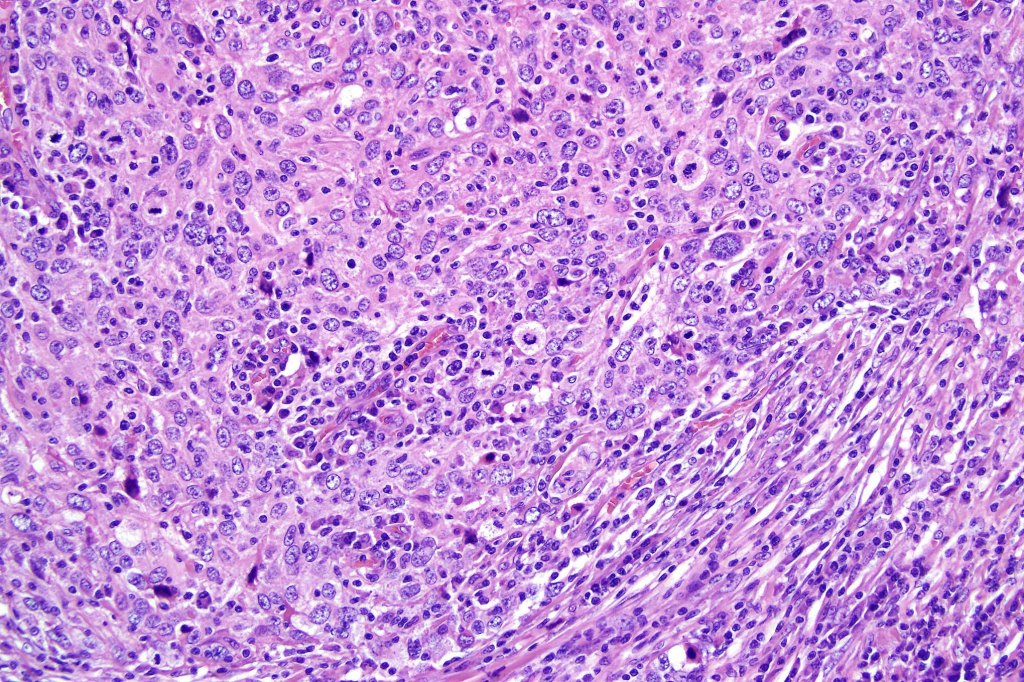

•Syncytial epithelial component in nests, cords or sheets surrounded by an intense lymphoplasmacytic infiltrate

•Epithelial cells are large with abundant cytoplasm and vesicular nuclei with conspicuous nucleoli

•Marked mitotic activity, variable pleomorphism

•Variable adnexal differentiation (follicular, sebaceous & eccrine)